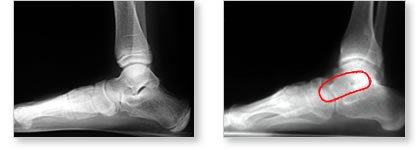

| These

are X- Rays looking at the side of the foot. On the foot on the

right, there is no space between the heel bone (calcaneus) and

the ankle bone (talus). The space is taken up by abnormal bone,

called a coalition. The foot on the left is a normal XR where

you can see the space between the calcaneus and the talus, and

the one on the right has the coalition circled in red. |